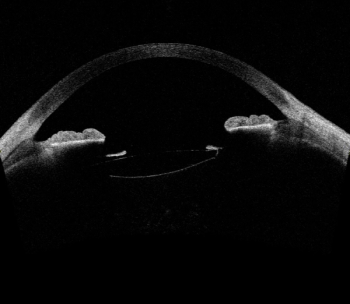

Laser technology has potential to modify IOL refractive index without change to lens shape